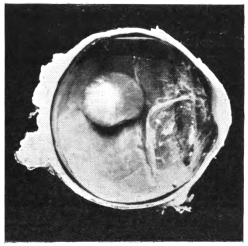

PLATE IV.

22.

LENS DISLOCATED BEHIND RETINA

curly bracket span

48

23.

FISTULA OF THE CORNEA

24.

CAPSULO-CORNEAL SYNECHIA

25.

RETINO-CORNEAL SYNECHIA

26.

SCLERAL FISTULA

27.

"    " (MAGNIFIED)